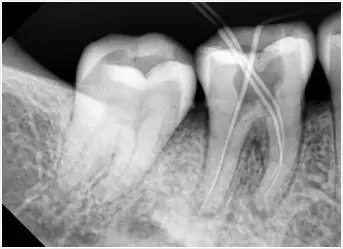

3、確定根管工作長度

應(yīng)用平行投照X線方法、根管長度測量儀確定根管度,最好插針拍X片。